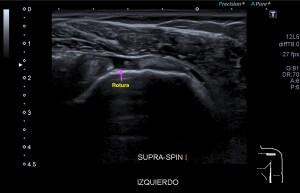

La radiografía revela aumento de las partes y se refrenda en la ecografía como puedes ver en la imagen aunque aún no hay afectación en el hueso en el caso que te presento hoy.

Ecografícamente y debido a su levedad, en el caso de hoy solo observamos cambios en las partes blandas de la cara lateral de la cabeza del quinto metatarsiano, este tejido se muestra heterogéneo, la cortical del hueso ligeramente prominente sin afectación de la misma.